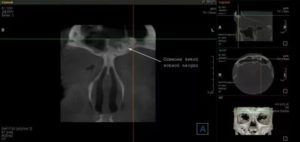

- компьютерная томография (КТ остеомы лобной доли);

При необходимости уточнения диагноза, для выявления окно клеток опухоли в области носа и околоносовых пазух, а также на костях черепа рекомендуется проведение компьютерной томографии.

- Компьютерная диагностика (КТ) выясняет расположение опухоли, размер очага и влияние на соседние структуры.

- На МРТ видна даже самая мелкая остеома. Метод выясняет структуру и плотность очага. По информативности не отличается от КТ.